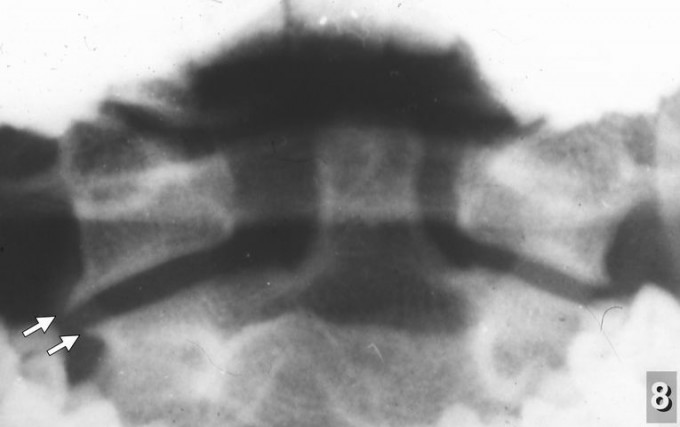

Хочу обратить внимание на следующее немаловажное обстоятельство. У детей с клиническими проявлениями последствий родовых травм шейного отдела уже с дошкольного возраста при рентгенографии наряду с симптомами перенесённых повреждений позвоночника нередко обнаруживался так называемый "спондилёз" - разрастание костных шипов (остеофитов) по краям тел позвонков (рентгенограмма 7) - признак хронического дегенеративно-дистрофического заболевания позвоночника, диагностируемого чаще всего после 40-50 лет. У взрослых при локализации процесса в шейном отделе характерными его проявлениями являются стойкий болевой синдром в шее, плечевом поясе, а также выраженные сосудистые нарушения головного мозга. В моих наблюдениях костные шипы на рентгенограммах у детей чаще всего обнаруживались в области I и II шейных позвонков (рентгенограмма 8 ) и являлись причиной упорных головных болей, острых нарушений мозгового кровообращения, "хруста" и болей в шее и другой патологии.

![]()

N-8 (306)готово" width="251" height="158" alt="Рентгенограмма 8" align="left" />Рентгенограмма 8 реб. М. 14 лет Выраженные остеофиты в области I - II шейных позвонков. Застарелый ротационный подвывих атланта.